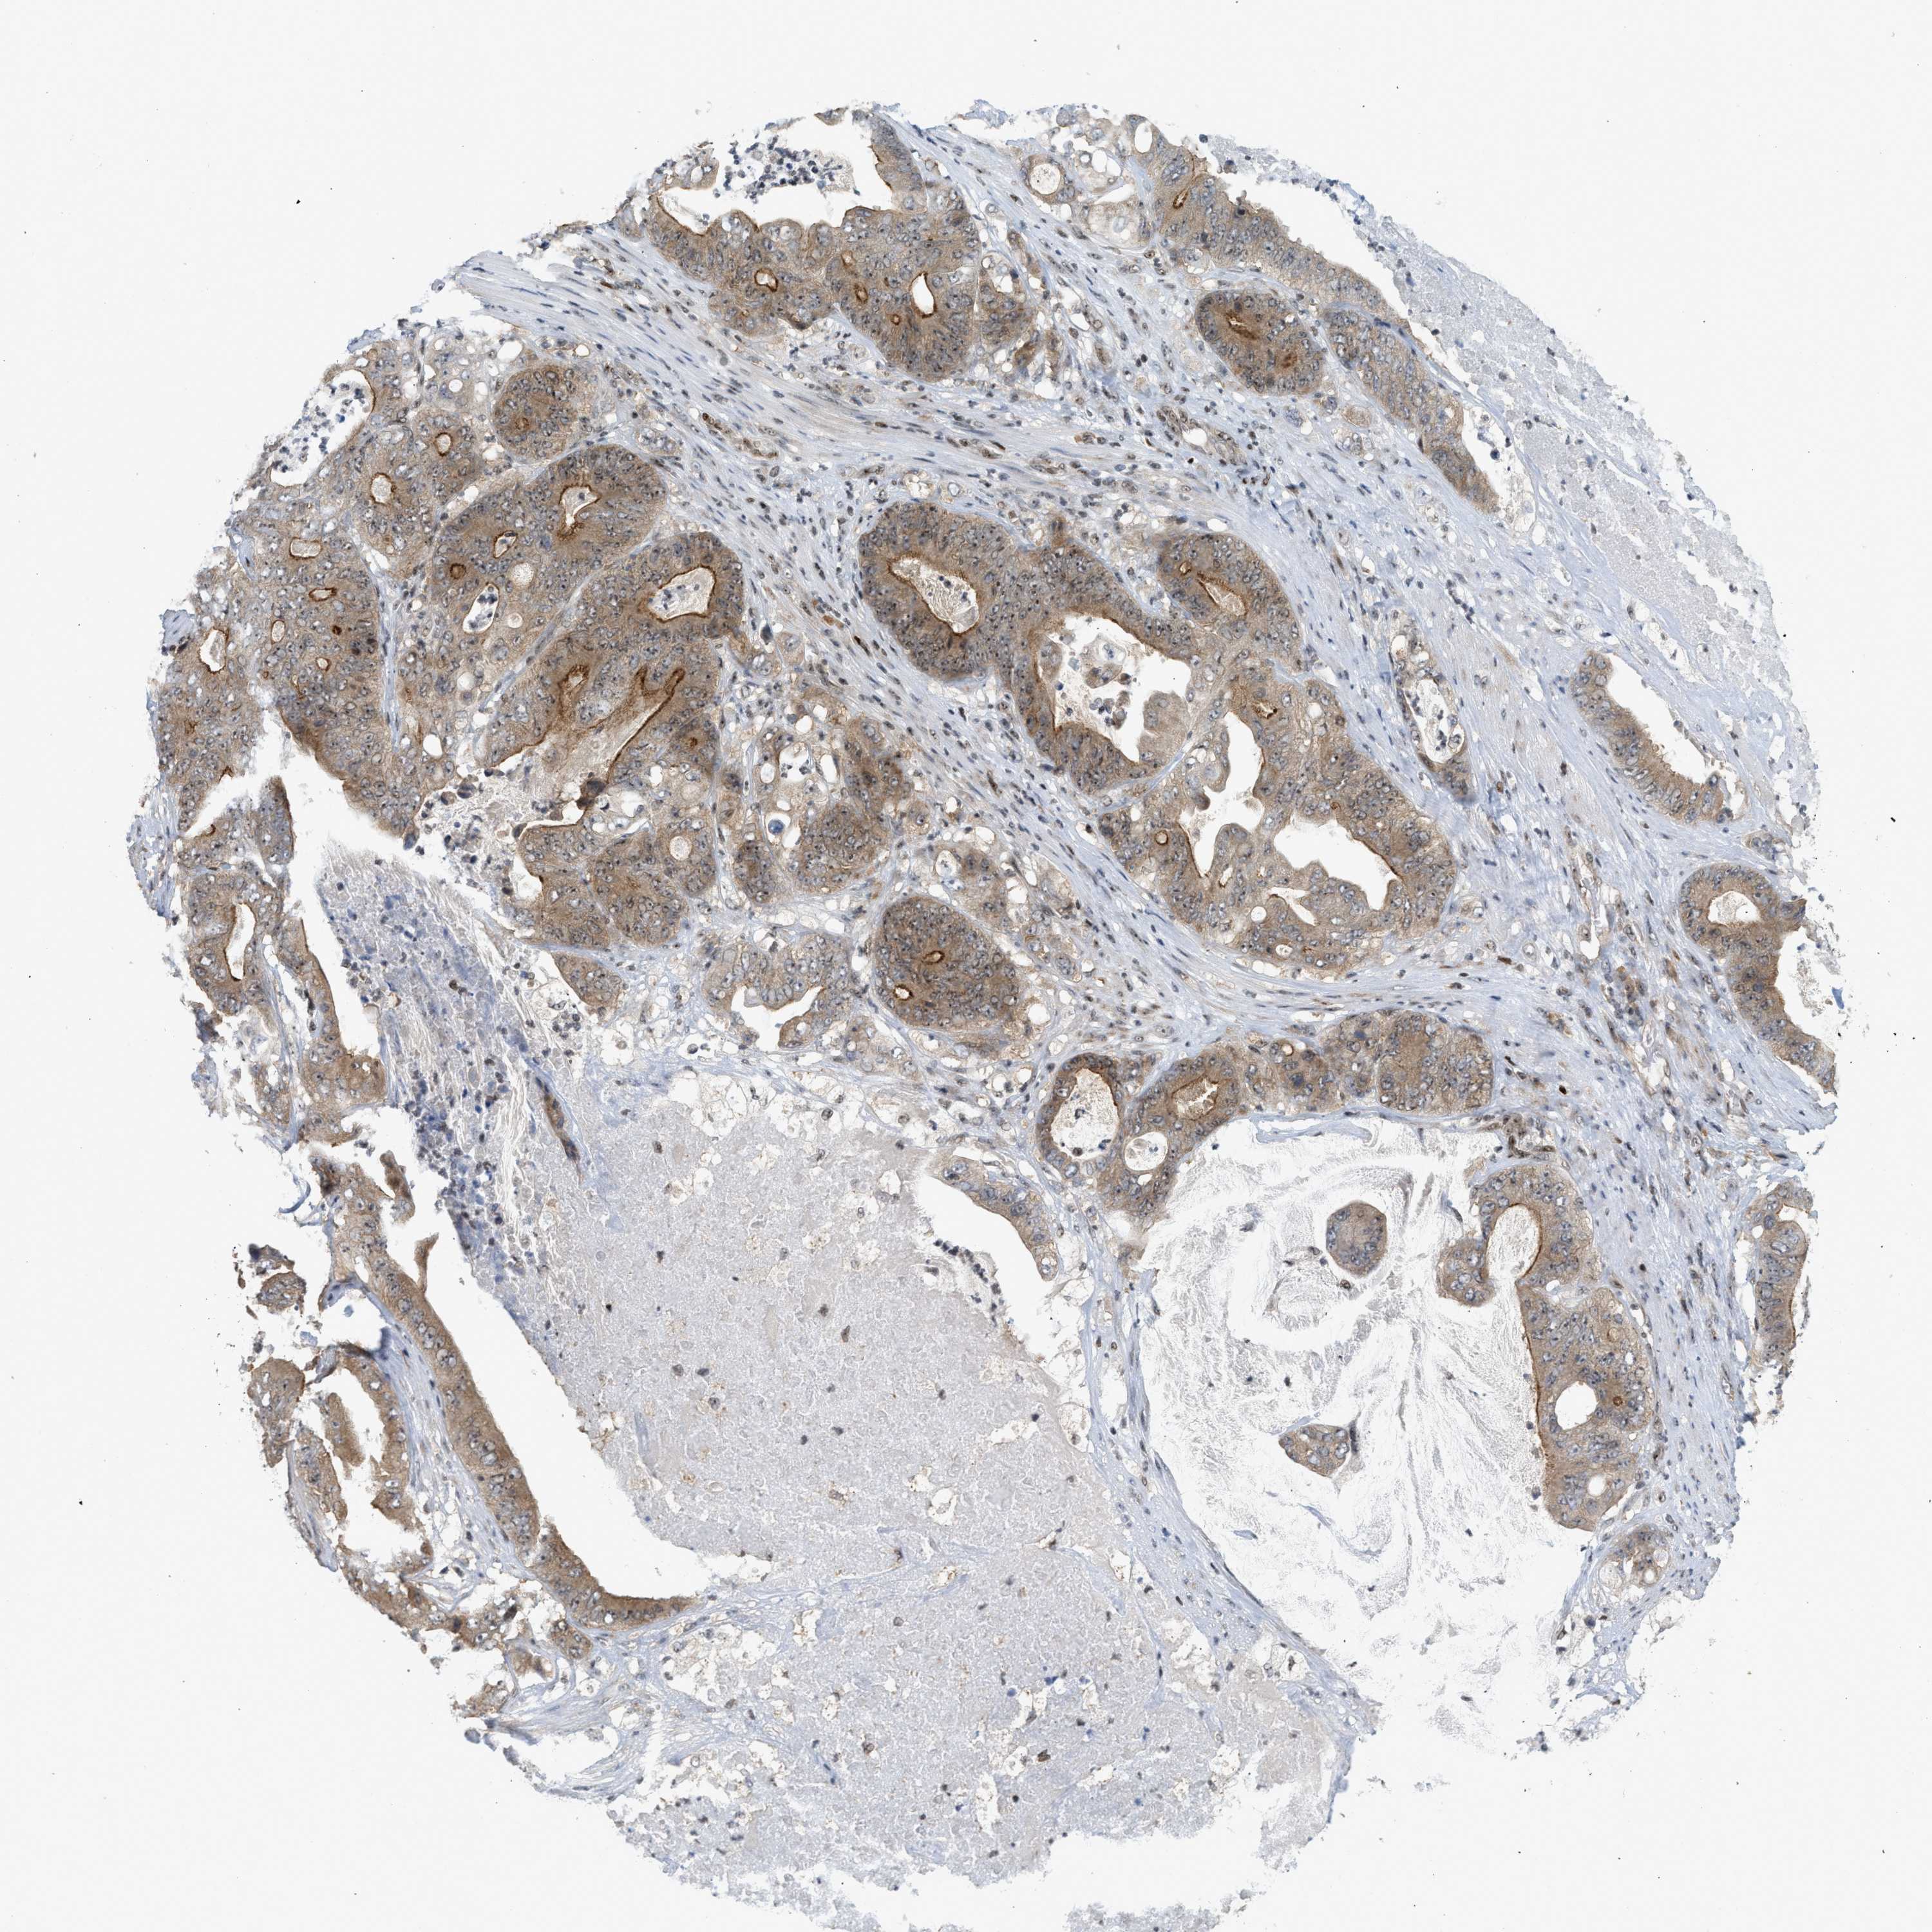

STOMACH CANCER - Protein expressioni

A mouse-over function shows sample information and annotation data. Click on an image to view it in a full screen mode. Samples can be filtered based on level of antibody staining by selecting one or several of the following categories: high, medium, low and not detected. The assay and annotation is described here.

Note that samples used for immunohistochemistry by the Human Protein Atlas do not correspond to samples in the TCGA dataset.

Antibody stainingi

Antibody staining in the annotated cell types in the current human tissue is reported as not detected, low, medium, or high, based on conventional immunohistochemistry profiling in selected tissues. This score is based on the combination of the staining intensity and fraction of stained cells.

Each image is clickable and will lead to virtual microscopy that enables deeper exploration of all samples and also displays staining intensity scores, fraction scores and subcellular localization as well as patient and tissue information for each sample.

Antibody HPA016736

Staining

High

Medium

Low

Not detected

Intensity

Strong

Moderate

Weak

Negative

Quantity

>75%

75%-25%

<25%

None

Location

Nuclear

Cytoplasmic/membranous

Cytoplasmic/membranous,nuclear

Adenocarcinoma, NOS